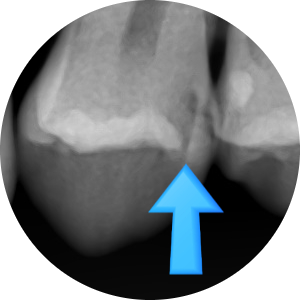

충치가 있다고 진단받았으나 겉에서 보이지 않는다고 방치하여

깨져서 온 사례

위 엑스레이 사진은 처음 방문하였을 때 엑스레이 사진입니다.

충치가 매우 심해 신경치료 해야 한다고 설명하였으나

환자분은 치아사진을 보면 치아가 썩은 것처럼 보이지 않는다면서(화살표 부분)

방치하다가 6개월이 지난 후 치아가 깨져서 오게 되었습니다.

이미 엑스레이 사진에서 충치가 매우 심함을 알 수 있고

치아 겉부분은 아주 얇게 남아있고 안은 무른 충치로 가득 차있음을 예상할 수 있습니다.